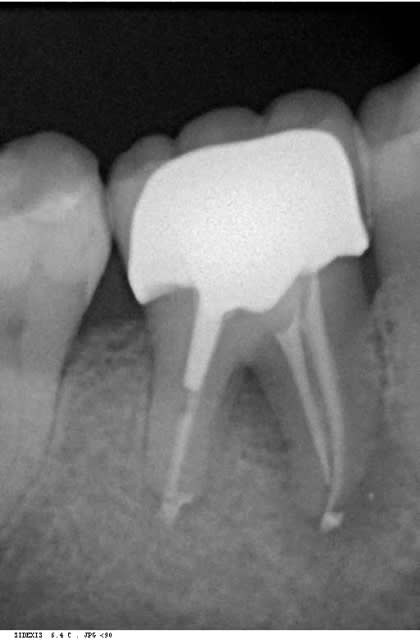

bon les pièces jointes d'alhoun.

décidément aussi nul en endo qu'en internet, et ton implant il est de traviole;)

Trev4 oye2tl - Eugenol

Trev5 lavbuq - Eugenol

Trev1 rgpu7x - Eugenol

Trev2 c5sddm - Eugenol

Trev3 wgcbda - Eugenol

çà doit être une déformation du cliché, regardes bien le premier cliché avec le pilier de cicatisation: on voit bien la partie cylindrique puis l'évasement.